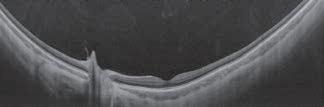

order to observe an individual mite in the clinical setting using a slit-lamp, the lash can be rotated at its base several times using tweezers, (termed the ‘Mastrota rotation’) until its tail emerges partially from the follicle. Another method is to exert ‘lateral tension’ on the lash to observe the emerging tail from the follicle opening without lash epilation.13

Lash epilation and in-vivo confocal microscopy are two research techniques used to count Demodex. In-vivo confocal microscopy involves applying the probe of the instrument to the eyelid margin. It provides complete observation of the lash contents, without the need to epilate the lash.10 In the lash epilation method, a lash with

cylindrical dandruff is epilated and observed under a microscope for the quantification of the mites attached to it. Both techniques are restricted to the research setting and are influenced by the lash chosen for observation, hence yielding variable results.14